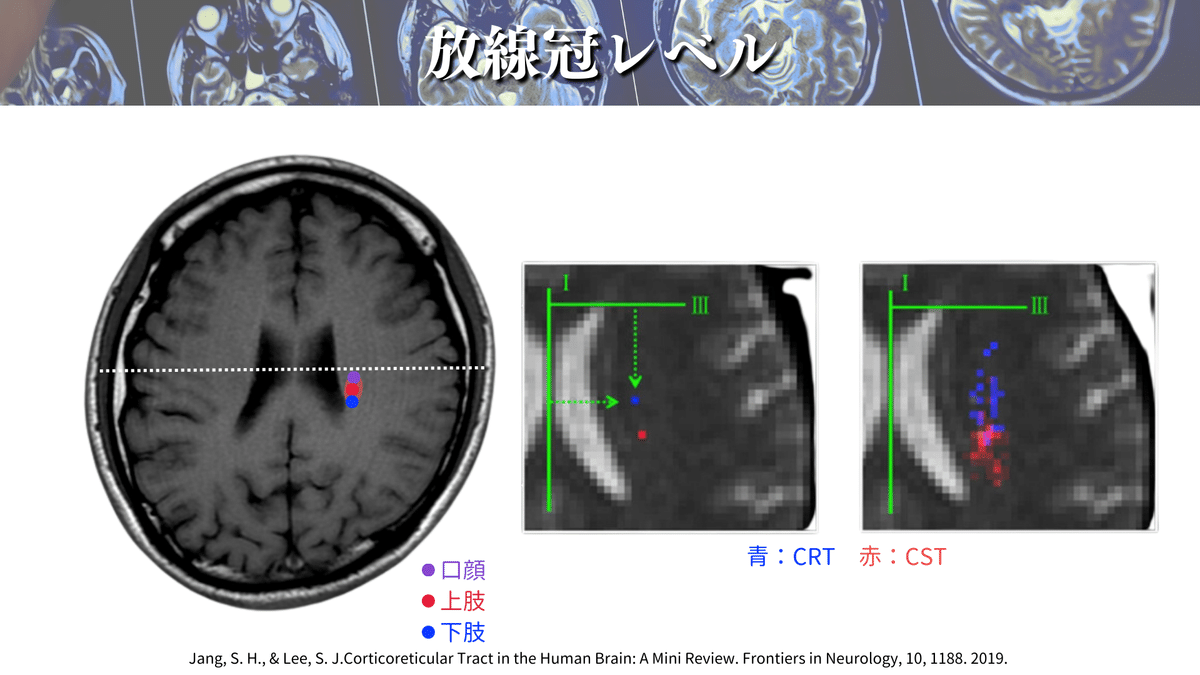

さらに解像度を上げると、、、🔍

こんな感じになります😳

やっぱり真ん中の線よりも下側にありそうですよね🤔

放線冠レベルの解説をしている論文は他にも多くあるので、オススメを紹介していきます✨

側脳室の前角や後角、側脳室の壁や島の縁などの距離から、口顔や上下肢のCSTの位置を計算する方法があります☝️

これによると、最も前外側に位置するのが口顔の線維であり、最も後内方に位置するのが下肢の線維ということが一目でわかりますね😳

これらのことから、大体この辺りを通るのかなということがわかったのではないでしょうか?🕵️(上図)